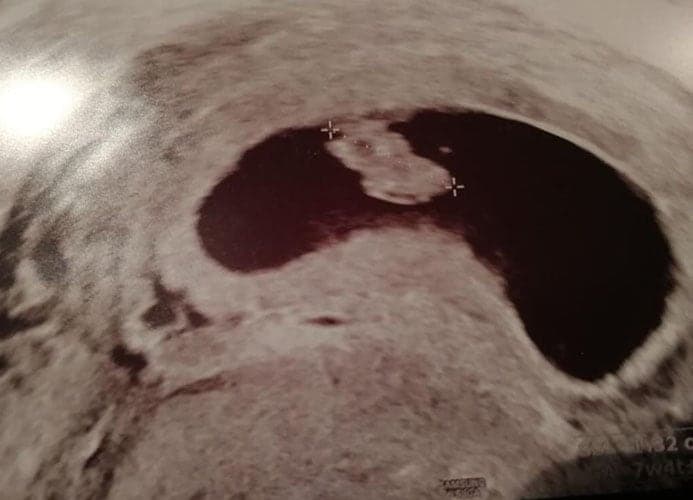

Ultraschallbilder aus dem 2. Trimester (13. bis 28. SSW)

Im 2. Trimester bekommt man oft die schönsten „Ganz-Körper“ Ultraschallbilder. Das Baby ist nun so groß, dass man alles gut erkennen kann und noch nicht zu groß, so dass es noch ganz auf das Bild passt. In dieser Zeit lässt sich meist das Geschlecht bestimmen, wobei manche Babys es einfach nicht preis geben wollen und sich immer so drehen, dass man nichts erkennen kann.